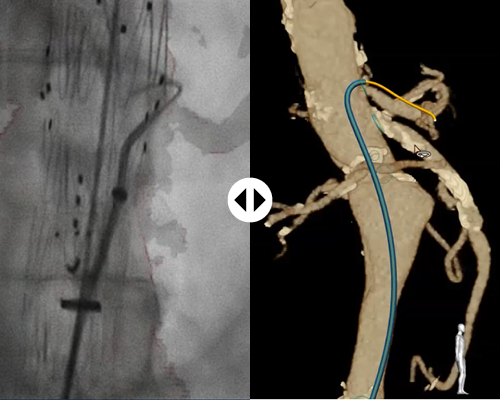

With FORS technology, clinicians can carry out parts of minimally-invasive interventions without the need for X- ray, which should minimize the risks associated with long-term radiation exposure.

Thanks to 3D Hub technology, you can continue to work with the catheters you’re already used to. The 3D Hub, in combination with FORS-enabled guidewires, enables your catheters to be visualized inside the body.

X-ray is still necessary to visualize the patient anatomy. FORS technology only visualizes devices. However, FORS has already been shown to reduce radiation exposure, for the patient and staff, during complex aortic procedures.